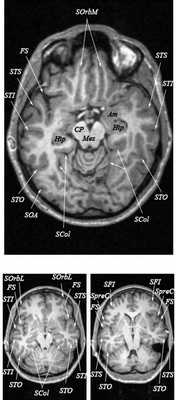

МРТ головного мозга. Т2-взвешенная аксиальная МРТ. Цветовая обработка изображения.

Знание анатомии мозга очень важно для правильной локализации патологических процессов. Ещё более важно оно для изучения самого мозга с помощью современных «функциональных» методов, таких как функциональная магнитно-резонансная томография (fMRI), и позитронно-эмиссионная томография. С анатомией мозга мы знакомимся ещё со студенческой скамьи и существует множество анатомических атласов, в том числе и поперечных сечений. Казалось бы, зачем ещё один? На самом деле, сравнение МРТ срезов с анатомическими приводит к множеству ошибок. Это связано как со специфическими особенностями получения МРТ изображений, так и с тем, что строение мозга очень индивидуально.

Представленная страница сайта основана на специальном изучении МРТ головного мозга здоровых лиц. Для этого изображения получали с минимальной величиной воксела (1 мм в каждом измерении), что исключало наслоения борозд. Каждая из структур прослеживалась в трёх реконструированных плоскостях путём её выделения с помощью компьютерной программы. Мы рассматривали различные анатомические варианты, что обсуждается в работе. В результате, учитывая вариабельность строения мозга, подобран условно «стандартный» мозг. Поскольку на сайте нереально представить 128 срезов в каждой из основных плоскостей, мы ограничились только каждым пятым срезом. Основные срезы в поперечной плоскости даны без наклона назад (угол 0º). Под ними для представления о изменении соотношения анатомических структур демонстрируются срезы, выполненные на тех же уровнях, но с наклонами назад -15º и -30º.

Поперечные (аксиальные) МРТ срезы головного мозга